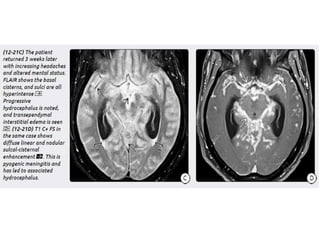

Tuberculous meningitis

• Tuberculous meningitis is the most common presentation

of intracranial tuberculosis, and usually refers to infection of

the leptomeninges.

• Tuberculous meningitis, although seen in all age groups, has a

peak incidence in childhood (particularly 0-4 years of age) in

high prevalence areas.

Tuberculous meningitis • Tuberculousmeningitis is the most common presentation of intracranial tuberculosis, and usually refers to infection of the leptomeninges. • Tuberculous meningitis, although seen in all age groups, has a peak incidence in childhood (particularly 0-4 years of age) in high prevalence areas.